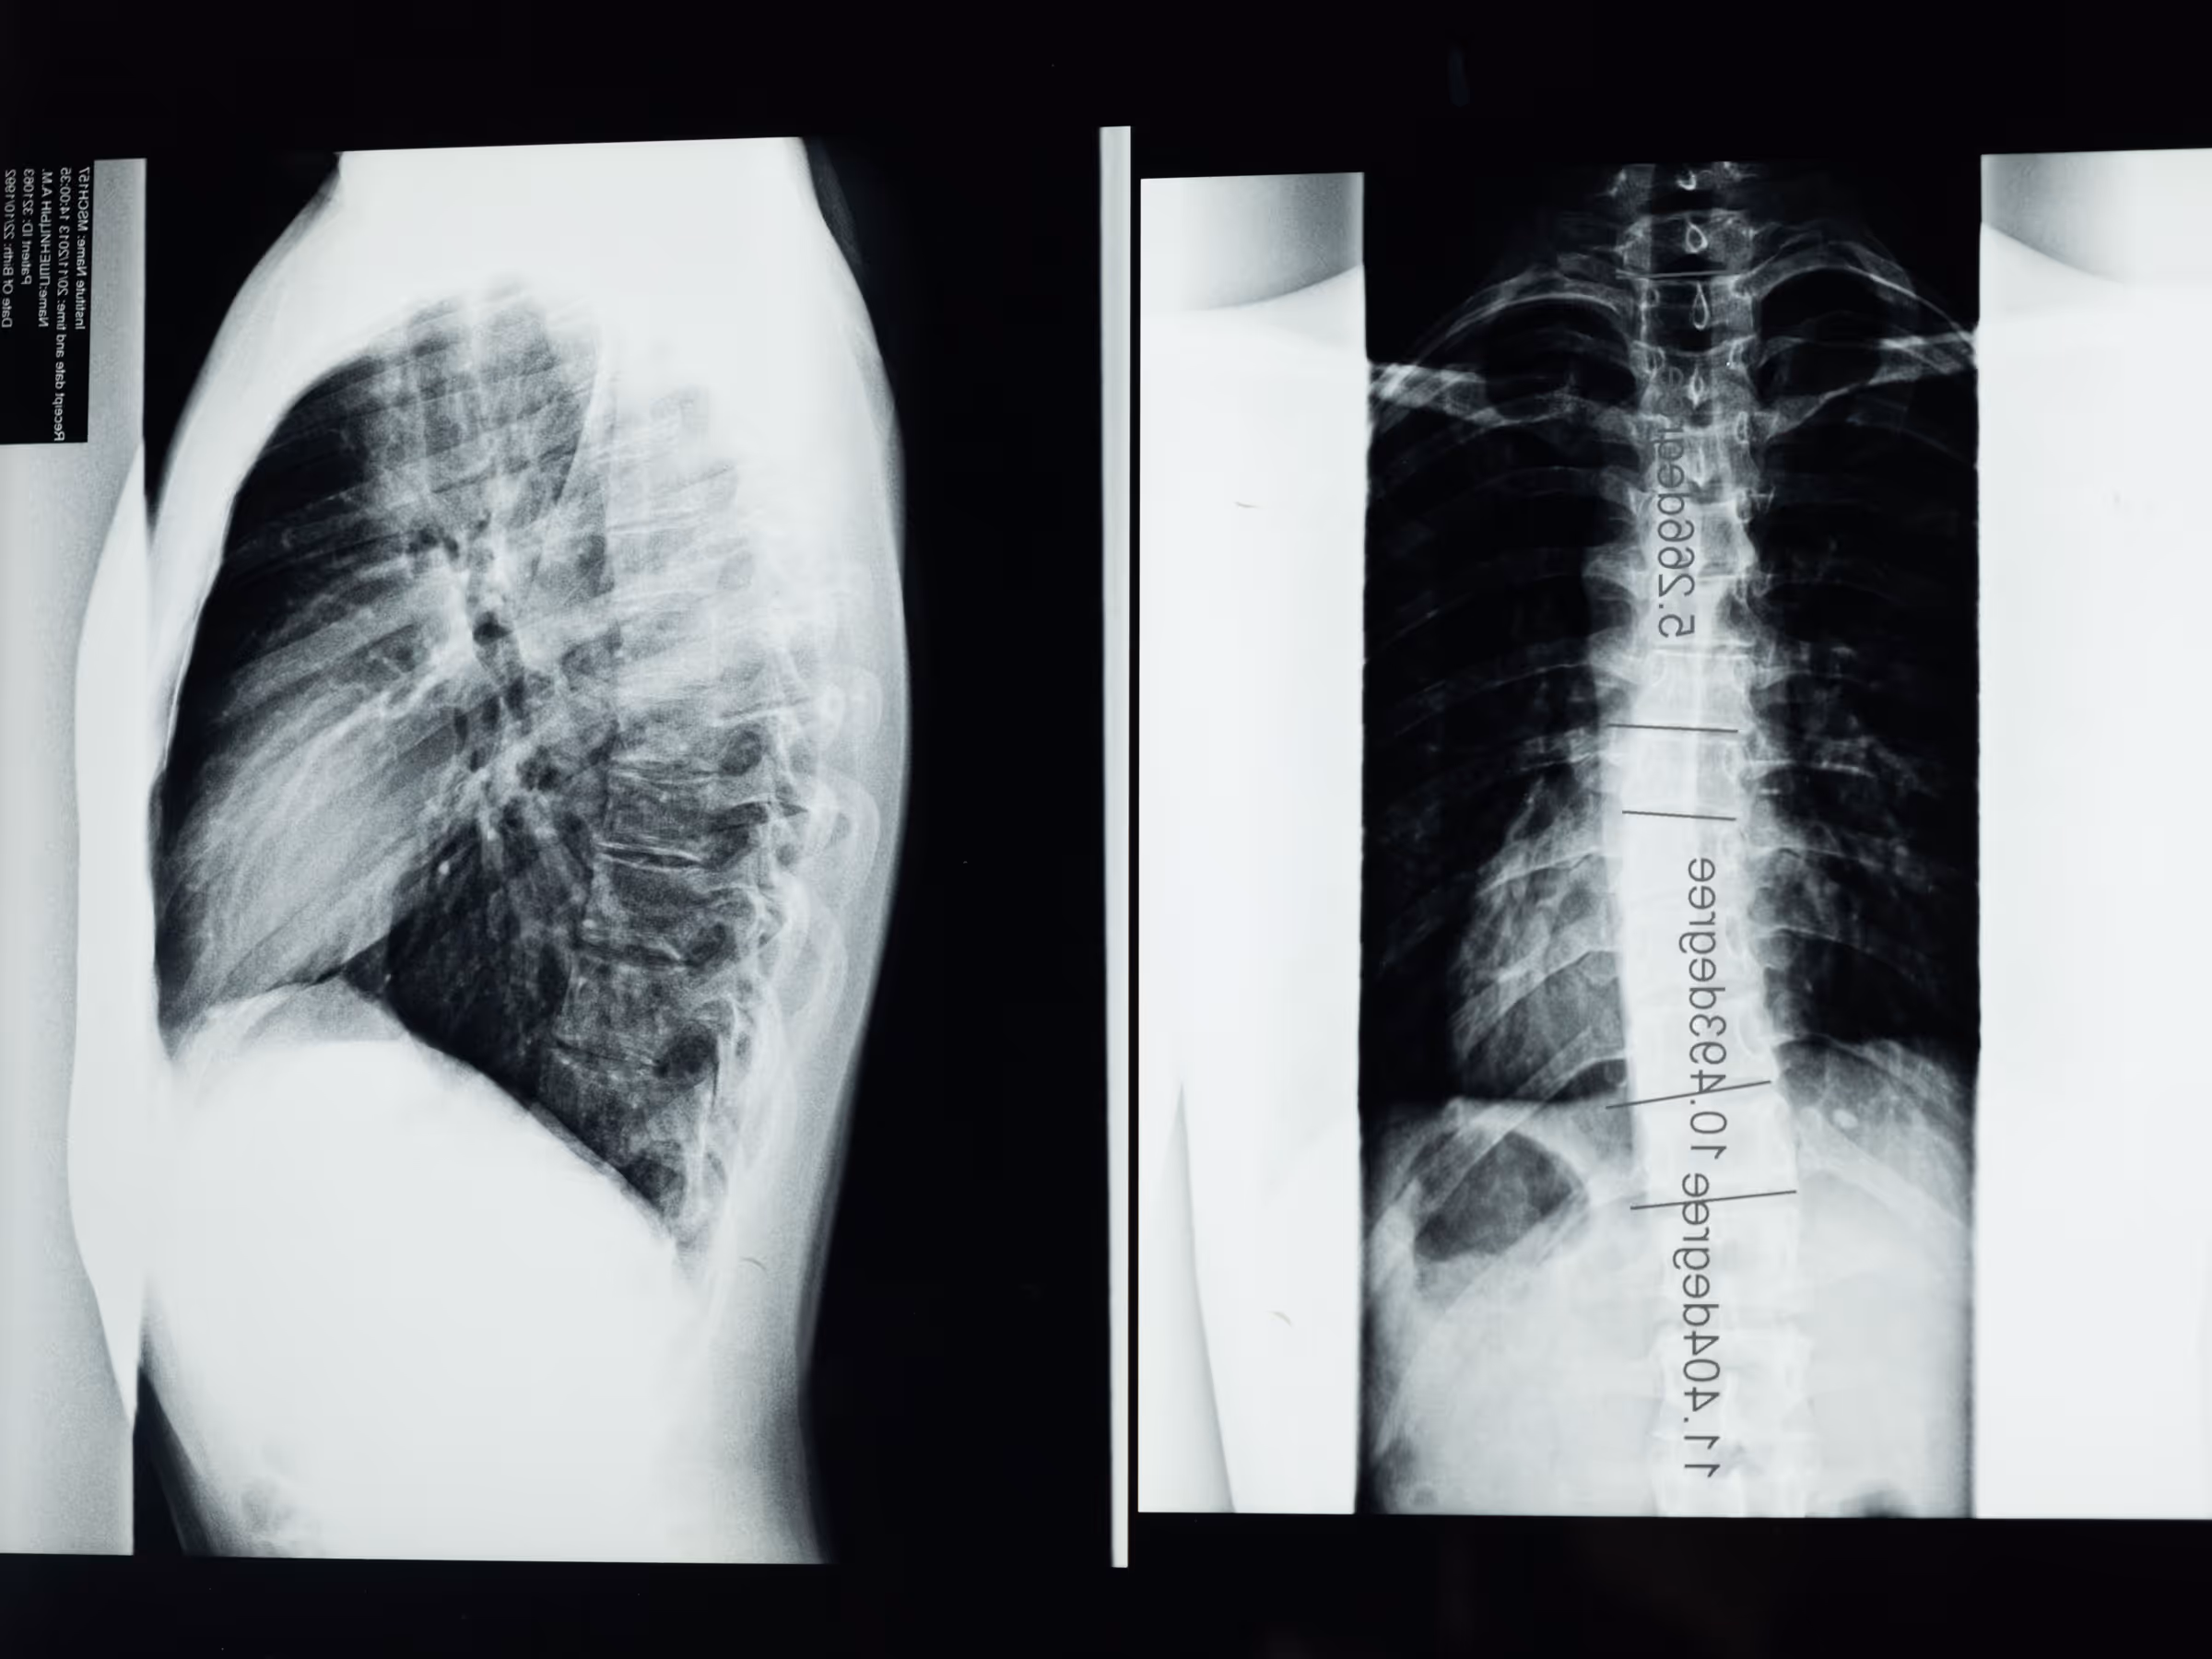

- Krümmung der Wirbelsäule

Die meisten Fälle von Skoliose haben leichte Ausprägungen. Manche Wirbelsäulendeformitäten verschlimmern sich jedoch mit zunehmendem Alter der Kinder. Eine schwere Skoliose kann zu Behinderungen führen, da eine starke Krümmung der Wirbelsäule den Raum im Brustkorb verkleinert und so die Lungenfunktion erschwert.

Was die Symptome anbelangt, so verursacht die Skoliose im Prinzip keine Schmerzen. Sie führt jedoch unter anderem zu Rückenschmerzen und Schmerzen im Lendenbereich. In mittelschweren und schweren Fällen kann sie zu anderen Komplikationen führen, z. B. zu Komplikationen der Atemwege. Aus diesem Grund ist es wichtig, die Skoliose frühzeitig zu diagnostizieren und so bald wie möglich mit einer physiotherapeutischen Behandlung zu beginnen, um das Fortschreiten der Skoliose zu verlangsamen und sie sogar teilweise oder ganz zu korrigieren und so eine Operation zu vermeiden.